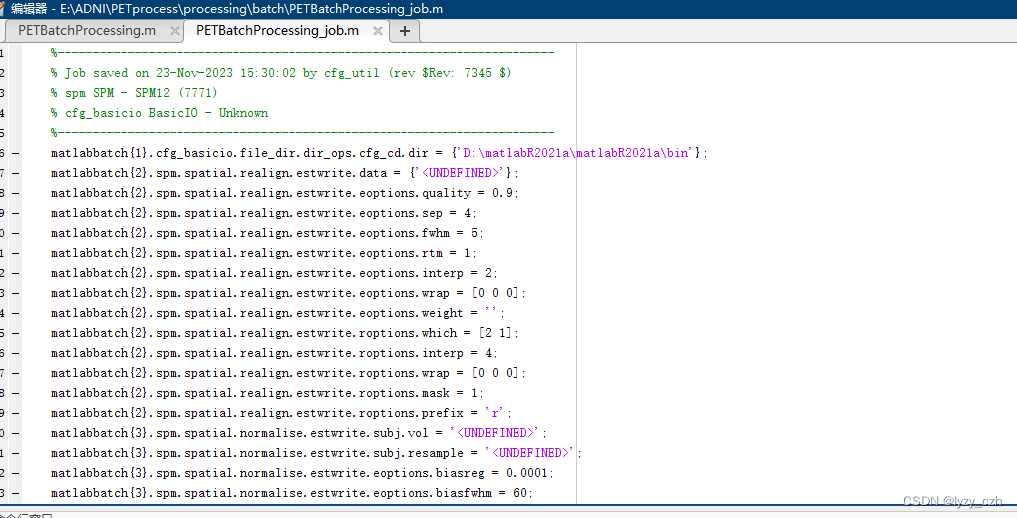

2、xxx_job.m文件代码如下(xxx是你自己的命名)

%-----------------------------------------------------------------------

% Job saved on 20-Nov-2023 19:01:02 by cfg_util (rev $Rev: 7345 $)

% spm SPM - SPM12 (7771)

% cfg_basicio BasicIO - Unknown

%-----------------------------------------------------------------------

matlabbatch{1}.cfg_basicio.file_dir.dir_ops.cfg_cd.dir = {'D:\matlabR2021a\matlabR2021a\bin'};

matlabbatch{2}.spm.spatial.realign.estwrite.data = {'<UNDEFINED>'};

matlabbatch{2}.spm.spatial.realign.estwrite.eoptions.quality = 0.9;

matlabbatch{2}.spm.spatial.realign.estwrite.eoptions.sep = 4;

matlabbatch{2}.spm.spatial.realign.estwrite.eoptions.fwhm = 5;

matlabbatch{2}.spm.spatial.realign.estwrite.eoptions.rtm = 1;

matlabbatch{2}.spm.spatial.realign.estwrite.eoptions.interp = 2;

matlabbatch{2}.spm.spatial.realign.estwrite.eoptions.wrap = [0 0 0];

matlabbatch{2}.spm.spatial.realign.estwrite.eoptions.weight = '';

matlabbatch{2}.spm.spatial.realign.estwrite.roptions.which = [2 1];

matlabbatch{2}.spm.spatial.realign.estwrite.roptions.interp = 4;

matlabbatch{2}.spm.spatial.realign.estwrite.roptions.wrap = [0 0 0];

matlabbatch{2}.spm.spatial.realign.estwrite.roptions.mask = 1;

matlabbatch{2}.spm.spatial.realign.estwrite.roptions.prefix = 'r';

matlabbatch{3}.spm.spatial.normalise.estwrite.subj.vol = '<UNDEFINED>';

matlabbatch{3}.spm.spatial.normalise.estwrite.subj.resample = '<UNDEFINED>';

matlabbatch{3}.spm.spatial.normalise.estwrite.eoptions.biasreg = 0.0001;

matlabbatch{3}.spm.spatial.normalise.estwrite.eoptions.biasfwhm = 60;